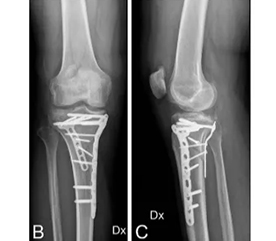

Case2